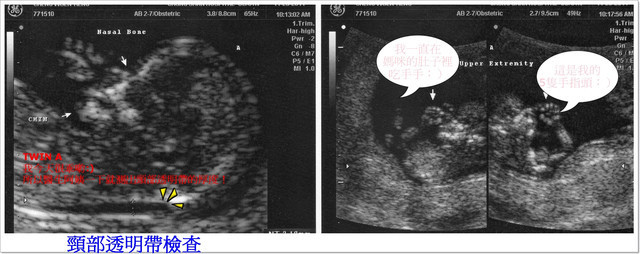

A寶寶身長:5.84公分(比一般值還大) 心跳:158/分

【頸部透明帶】檢查可以提早發現染色體異常及唐氏症,

所謂【頸部透明帶】(Nuchal translucency NT)

是指在第一孕期利用超音波觀察於胎兒頸部後的皮下積水的空隙,

在超音波掃描時會呈現透明帶狀,再測量介於皮膚和組織之間的最大空隙厚度。

如果厚度超過2.5mm或是3mm,就代表胎兒屬於唐氏症的高危險群,

也就是胎兒後頸部透明帶越厚,罹患有先天性疾病的機率越高,

此時,醫師會建議進一步用絨毛膜採樣或是羊膜穿刺檢查胎兒染色體。

這項檢查花了快一個小時的時間,以往照超音波大概都只花不到10分鐘就結束,

通常都只量了寶寶的身長,確定寶寶們心跳之後就結束,這次的檢查非常非常的仔細,

超音波醫生非常仔細的從寶寶們的頭圍、鼻梁骨角度、手臂和大腿骨長度、腦部發育狀況、

臍帶血流,心跳的頻率,還有媽咪的子宮動靜脈及子宮頸長度等等,都一一仔細的檢查,

連寶寶們的手指頭和腳指頭也都是一根根的數給我們聽哦!

才到了最後的重點-「頸部透明帶厚度檢驗」,

這個透明帶需要寶寶呈現自然平躺的姿勢才能測量得到哦!

寶貝們很乖的,很快的就讓醫生測量到,

只有B寶寶比較頑皮,一直貼著羊膜,醫生不斷的又揉又震動我的肚子,

希望寶寶可以乖乖的躺好,果然寶寶在躺下來的時候後頸部出現一條黑色的帶子,

就是要測量這條帶子的厚度,要是太厚(超過3mm)就表示有唐氏症的危險哦!

呼~還好!最後測量的數值在標準範圍之內!

今天檢驗出來結果,每一項都是正常的,真是太好了((開心ing))